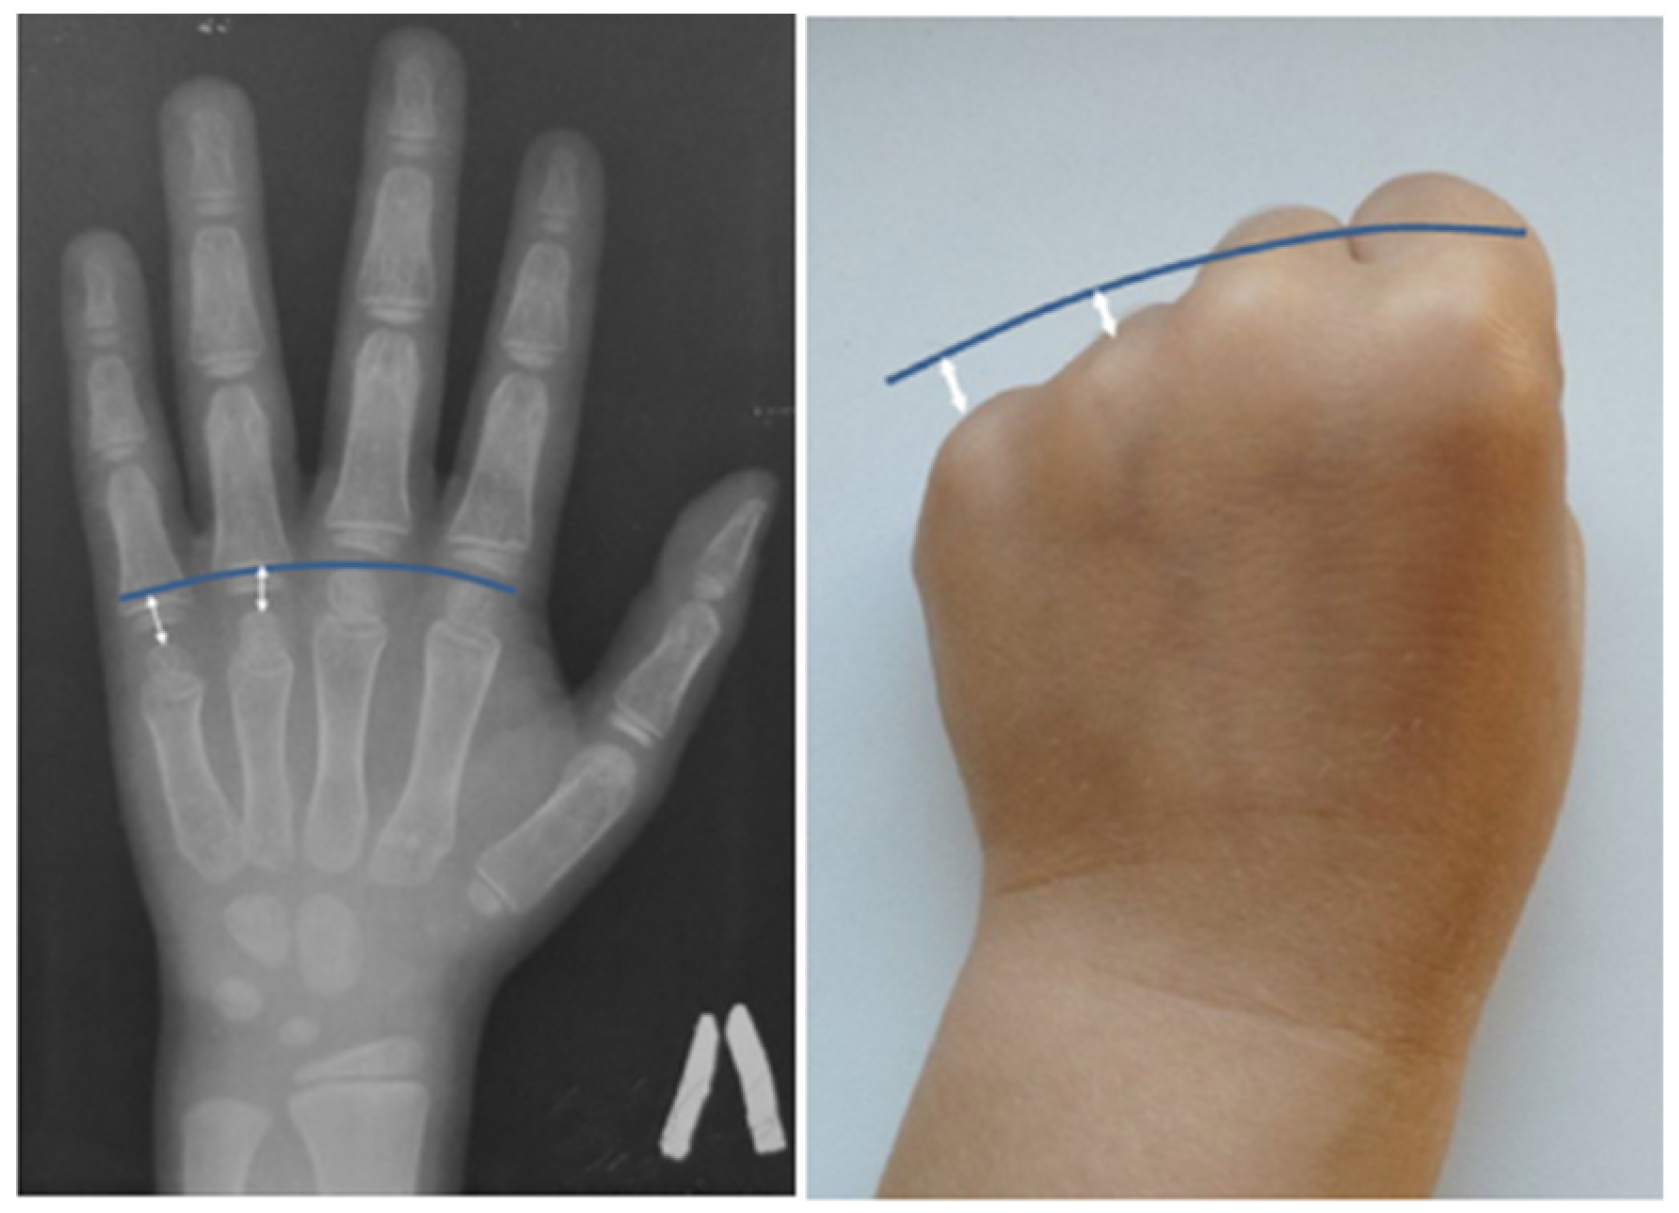

An X-ray examination of the wrist bones, performed due to short stature (−1.9 standard deviations) in the cousin of the F1 III-1 proband, revealed relative shortening of the fourth and fifth metacarpals (Figure 3).

The analysis of phenotypic manifestations in the patients observed in this study and presented in the literature indicates polymorphism of the clinical manifestations of the CDL in patients with the recurrent variant in the SGMS2 gene. The presence of significant clinical polymorphism (including intrafamilial) in all of these cases allows us to conclude the possible effect of the genetic background and epigenetic modifiers on the formation of the disease phenotype. In most patients, the first fractures occur in childhood; however, the age of clinical manifestation widely varies. Differences in the height indicators of patients with the presence of multiple fractures were noted. In some patients, height was within the normal range, while in others, the growth was reduced by more than 2 SD. Along with skeleton involvement, some patients have symptoms of damage to the nervous system in the form of migraine, cephalgia, recurring paralysis of the facial, trigeminal, and oculomotor nerves, carpal tunnel syndrome, dystonia, and tremor. However, the severity of skeleton and nervous system involvement in patients with nonsense and two missense variants differed significantly. In two patients with p.Ile62Ser or Met64Arg variants reported in the literature, spontaneous fractures occurred in the neonatal period and led to decreased height as a result of deformations of the spine and limbs. The radiological examination revealed signs of spondylometaphyseal dysplasia. The more pronounced symptoms of nervous system damage were also noted. In addition to transient cranial nerves paralysis, patients were diagnosed with sensory neuropathy, hearing loss, and tendon hyporeflexia. The pathogenesis of CDL has not been fully understood yet, but it is assumed that neurological symptoms are associated with a dysfunction of the gene product, the enzyme sphingomyelin synthase, which is involved in the synthesis of myelin in the structures of the nervous system. Some of the patients examined by us (4/11) had transient recurrent facial nerve paralysis in adulthood, affecting both the upper and lower parts of the face that resolved on their own within a month. Two patients from the second family suffered from headaches since childhood. In addition, the presence of congenital bilateral glaucoma in one of the examined patients was noted. Interestingly, congenital glaucoma was also reported in one patient with CDL in a study by Pekkin M. et al. in 2019 [4]. Undoubtedly, this observation requires further accumulation of clinical data in patients with CDL. It should be noted that in the spectrum of phenotypic manifestations, serious damage to the teeth was found in some of the patients with a severe course of the disease, which led to their early destruction, wearing out of the incisal edges, and yellowing of the enamel, although other patients did not have the signs of teeth involvement. Another additional finding in CDL was a shortening of the fourth–fifth metacarpals previously reported by Jaakkola E. et al. [15]. We were able to detect similar features in the cousin of the proband in the first family. As the disease is quite rare, it is necessary to describe in detail all the phenotypic characteristics of patients with various types of variants in the SGMS2 gene, which will help to optimize its diagnosis.

Figure 3. Radiograph and appearance of the hand of the 7 y.o. patient (F1 III-1) with brachymetacarpia of the fourth and fifth digits: relative shortening (white arrows) of the fourth and fifth metacarpals to compare with the metacarpal heads line (blue line).